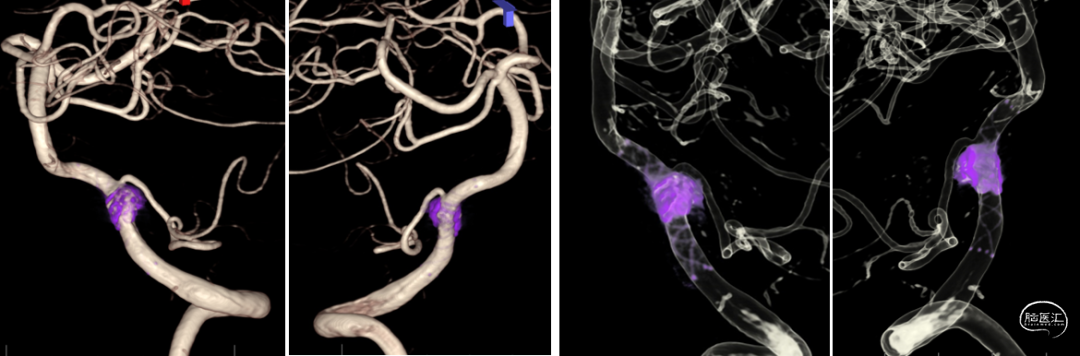

CTA:

右侧椎动脉(优势侧)V4段梭形动脉瘤,

左侧椎动脉纤细,后交通动脉未显影。

影像科提供的重建图像就像美颜照片,虽然好看,但丢失了诸多细节。

我们使用影像工作站重建的图像能够看到更多细节:

动脉瘤处有明显的凹陷,考虑为动脉夹层的内膜瓣;动脉瘤累及小脑后下动脉(PICA)的开口。

3D造影:动脉瘤处有明显的凹陷,符合夹层内膜瓣表现;PICA从动脉瘤远端发出,动脉瘤大小约6.5×12.8mm,受累椎动脉直径约4.3mm,覆盖远近端达正常血管约需30mm支架长度。